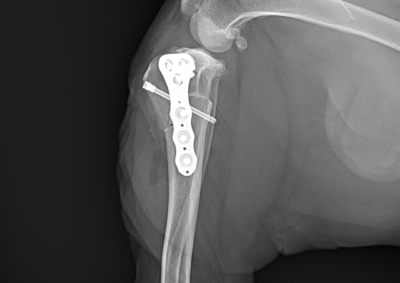

整形外科 注意 ボタンをクリックした先に、治療中および手術中の画像が説明で使用されている場合がございます。 そのような画像に弱い方は閲覧なさらないようお願いいたします。 整形外科 若齢犬の橈骨固定術 #271 整形外科 前十字靭帯断裂(中型犬)に対するCBLO #255 整形外科 超小型犬に対する上腕骨遠位Y字骨折 整形外科 大型犬の前十字靭帯疾患(慢性経過)に対するCBLO #254 整形外科 橈骨固定術 #270 整形外科 膝蓋骨内方脱臼に対する人工滑車置換術 PGR #23 整形外科 犬の前十字靭帯(疾患)部分断裂に対するCBLO #253 整形外科 犬の前十字靭帯断裂に対するCBLO #252 整形外科 膝蓋骨内方脱臼+前十字靭帯断裂に対するPGR#22・LSS 整形外科 大腿骨骨折 整形外科 橈骨固定術 #269 整形外科 上腕骨外顆骨折の癒合不全 123456> 症例カテゴリー 放射線治療整形外科軟部組織外科脳神経外科内科腫瘍外科救急・集中治療リハビリテーション科腫瘍内科内視鏡科脳神経科呼吸器外科中医・漢方猫の腎移植循環器科